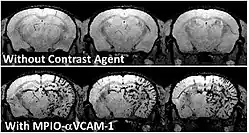

- des marqueurs, sondes ou traceurs, de natures diverses (colorants, produit de contraste, marqueur radioactifs ou opaques au rayons X, émulsion fluorescente telle que la sentidye, des protéines fluorescentes éventuellement produites in situ par l'organisme, après qu'il a été génétiquement modifiée (souris de laboratoire par exemple).

Ces produits (injectés ou ingérés ou produits par un organisme génétiquement modifié pour cela) visent un organe, un type de cellule, ou une molécule particulière qui sera ainsi mise en évidence par l'imagerie.